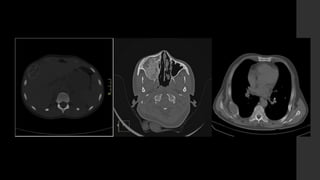

Osteoma.

• RX 

Masa densa, esclerótica con aspecto de marfil, con

márgenes definidos, unida al hueso.

• TC 

Es eficaz para demostrar la ausencia de invasión cortical.

• IRM

Imágenes con señal baja en T1 y T2 sin realce.

Adam Greenspan et al. Tumores osteoblásticos (formadores de hueso). Tumores de huesos y articulaciones. Capítulo 2. PP. 25 – 26.